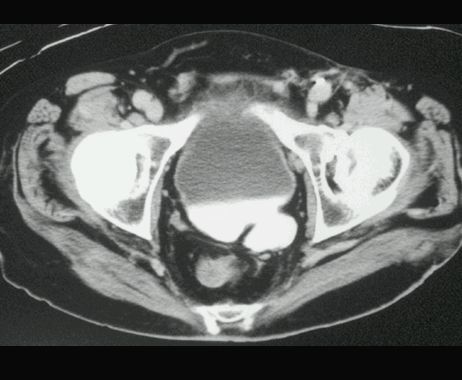

UCHYŁEK PĘCHERZA MOCZOWEGO

TK